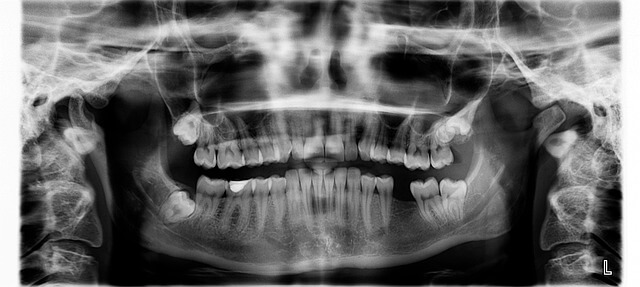

먼저 인레이는 충치나 손상 부위를 메우는 보철 치료입니다. 단순히 구멍을 메우는 충전 치료보다 더 정밀하게 제작해 맞춤형으로 붙이는 방식이에요. 저는 처음에 치아가 깨져서 걱정했지만, 인레이로 손상된 부분만 보강하니 자연스럽고 통증도 거의 없었습니다. 이 치료는 치아 구조를 최대한 살리면서 복원하고 싶을 때 추천됩니다.

특히 인레이는 깨진 부분이 크지 않은 어금니에 적합합니다. 직접 받아보니 씹는 감도 자연스럽고, 음식물이 낄 일도 적었어요. 요즘은 디지털 스캔을 활용해 정밀하게 제작하기 때문에, 과거보다 정확도도 훨씬 높아졌습니다.

인레이 치료는 생각보다 간단하지만, 2회 내원이 필요했습니다. 처음 방문 때는 충치 부위를 제거하고 본을 떴어요. 이때 치아 모양을 3D 스캐너로 촬영해서 맞춤형 인레이가 제작됩니다. 일주일 뒤 두 번째 내원에서 실제 인레이를 부착했는데, 붙일 때 통증은 전혀 없었어요. 접착 후 검진까지 30분도 안 걸렸습니다.